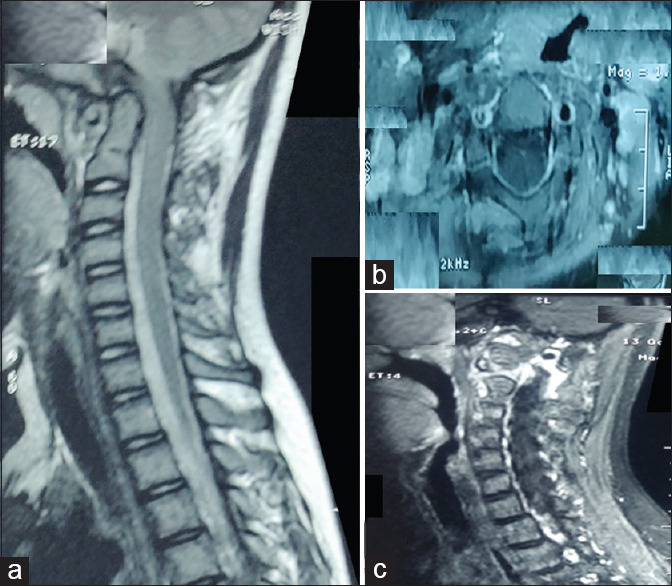

Figure 1.

(a) T2-weighted magnetic resonance imaging of cervical spine, sagittal image shows narrowing at craniovertebral junction with anterior compression of cord at cervicomedullary junction but no intensity changes are seen. (b) T1-contrast, axial image showing multiple enlarged homogenously enhancing lymph-nodes. (c) T1-contrast, sagittal paramedian image showing enhancement at craniovertebral junction